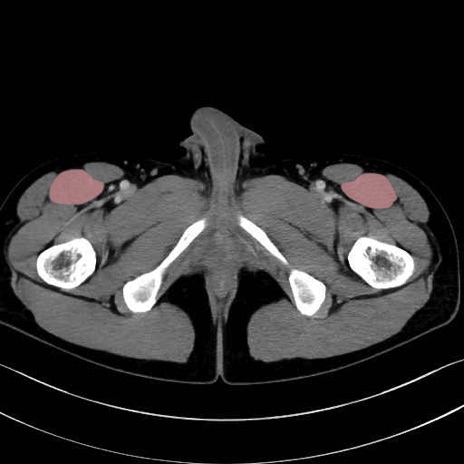

大腿直筋 (Rectus femoris)